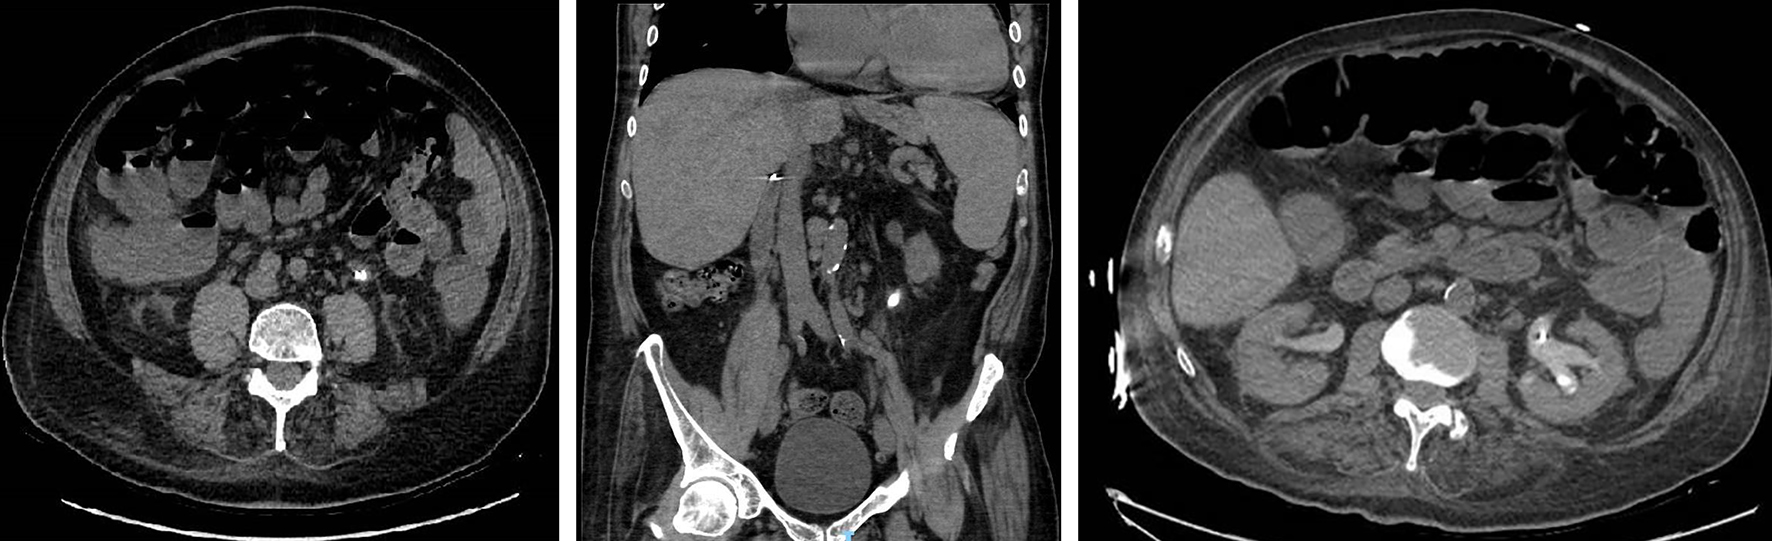

Abdominal and pelvic computed tomography (CT) scan was performed due to pelvic/flank pain but also to further assess the urine analysis (U/A) that showed 80 - 100 red blood count (RBC), 80 - 100 white blood count (WBC) and numerous uric acid crystals. Images came out significant for an obstructive stone in the left proximal ureter measuring 2.3 × 1 cm with subsequent left hydronephrosis. Hence the patient underwent JJ catheter insertion (Fig. 1).

![]() Click for large image | Figure 1. Figure 1. Obstructive stone at the left proximal ureter measuring 2.3 × 1 cm with surrounding fat stranding and hydronephrosis in axial and coronal view. |